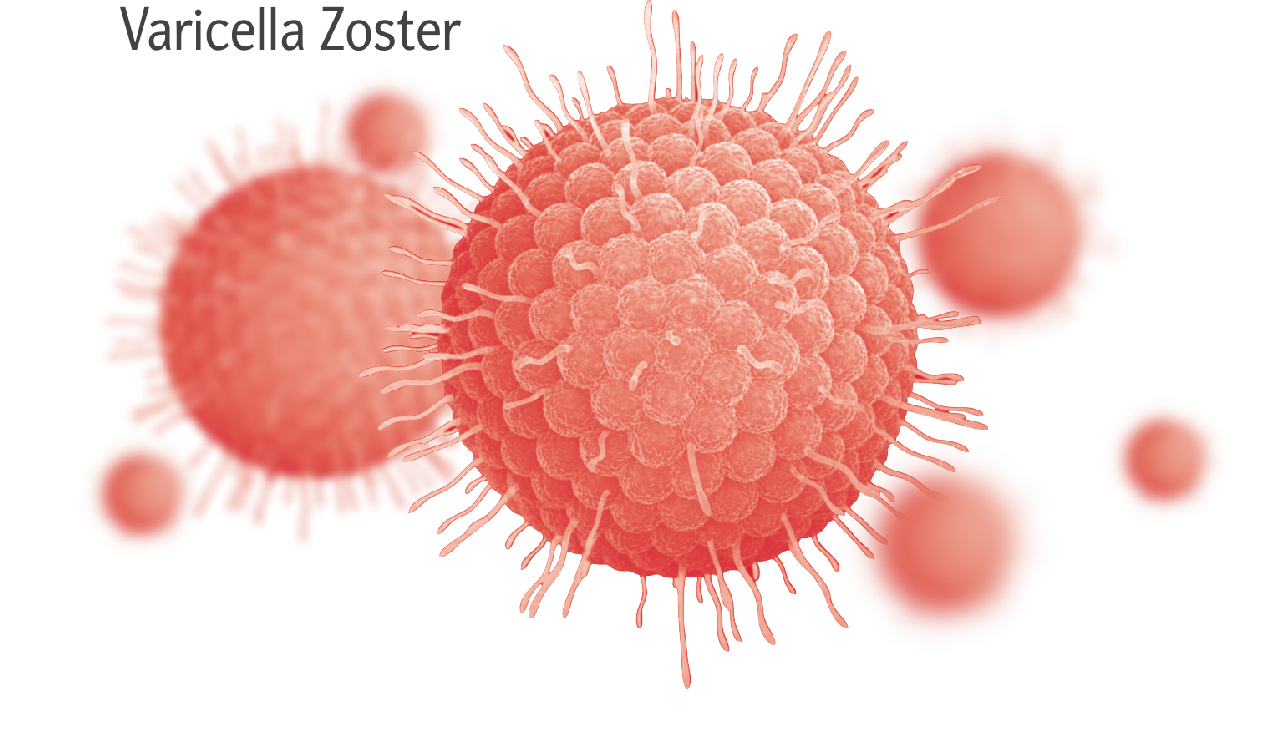

Медицинские снимки и изображения опоясывающего герпес вируса

Раздел: Фотодневник открытий